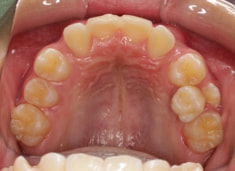

治療前

治療開始時